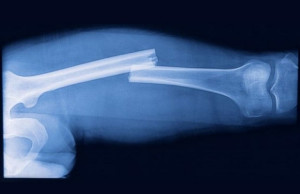

В первом случае, когда смещение костных отломков превышает треть диаметра кости, нужна операция. Если это упустить из виду, могут быть последствия, например, образование ложного сустава или развитие замедленной консолидации. В связи с этим процесс костного сращения играет очень важную роль в лечении и каждый пациент, которому назначается эта операция, должен это понимать. Любой перелом лечится в согласии со следующими принципами:

Открытая репозиция применяется в случае нарушения кожных покровов. Это главное показание. Другой диагноз, при котором назначается данный метод лечения, — невправляемый, множественный перелом. Это связано с тем, что при наличии множественных обломков сопоставить их не получится, если не оголить костную ткань. Когда какой-то костный фрагмент прикреплен к мышцам, закрытое вмешательство бессмысленно, потому что, как только мышца начинает напрягаться, обломок сдвигается заново. Именно поэтому требуется более серьезная операция.

Если происходит травма длинных костей и смещение, когда конец одного отломка находится на другом, требуется вытяжение. Ошибка, которая может быть допущена — слишком короткое вытяжение. Большая часть переломов обладает неправильной формой и несколько выступов, которые не позволяют отломкам встать в нужное положение. Следует немного перетянуть конечность, чтобы нарушить это сцепление, поэтому необходимо выполнять постоянное натяжение в течение пяти или десяти минут.